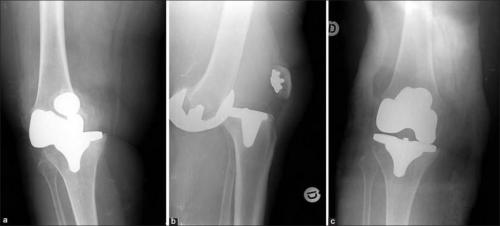

Также существует заместительная артропластика или замена сустава, что намного серьезнее. Врачи удаляют некоторые части больного сустава и заменяют их имплантами, выполненными из специального металлического сплава или пластмассы. Она чаще всего проводится на бедренном или коленном суставе, однако может быть проведена не только с ними.

- Замена коленного сустава. Во время этой операции все сочленение или его части заменяются эндопротезом. Для изготовления протезов используют различные материалы, размер подбирается индивидуально. Эндопротезирование с успехом решает вопрос, как восстановить утраченные функции колена.